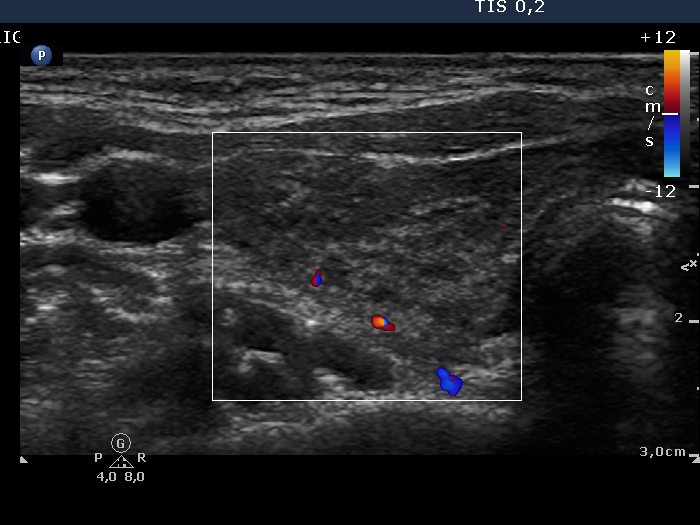

Chronic lymphocytic thyroiditis - Case 2. |

Ultrasonography: both thyroids were hypoechogenic with fibrotic changes. Based on the previously described "nodule", the fibrotic changes were more pronounced. This area did not fit a nodule.